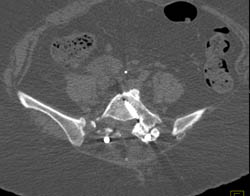

Chordoma